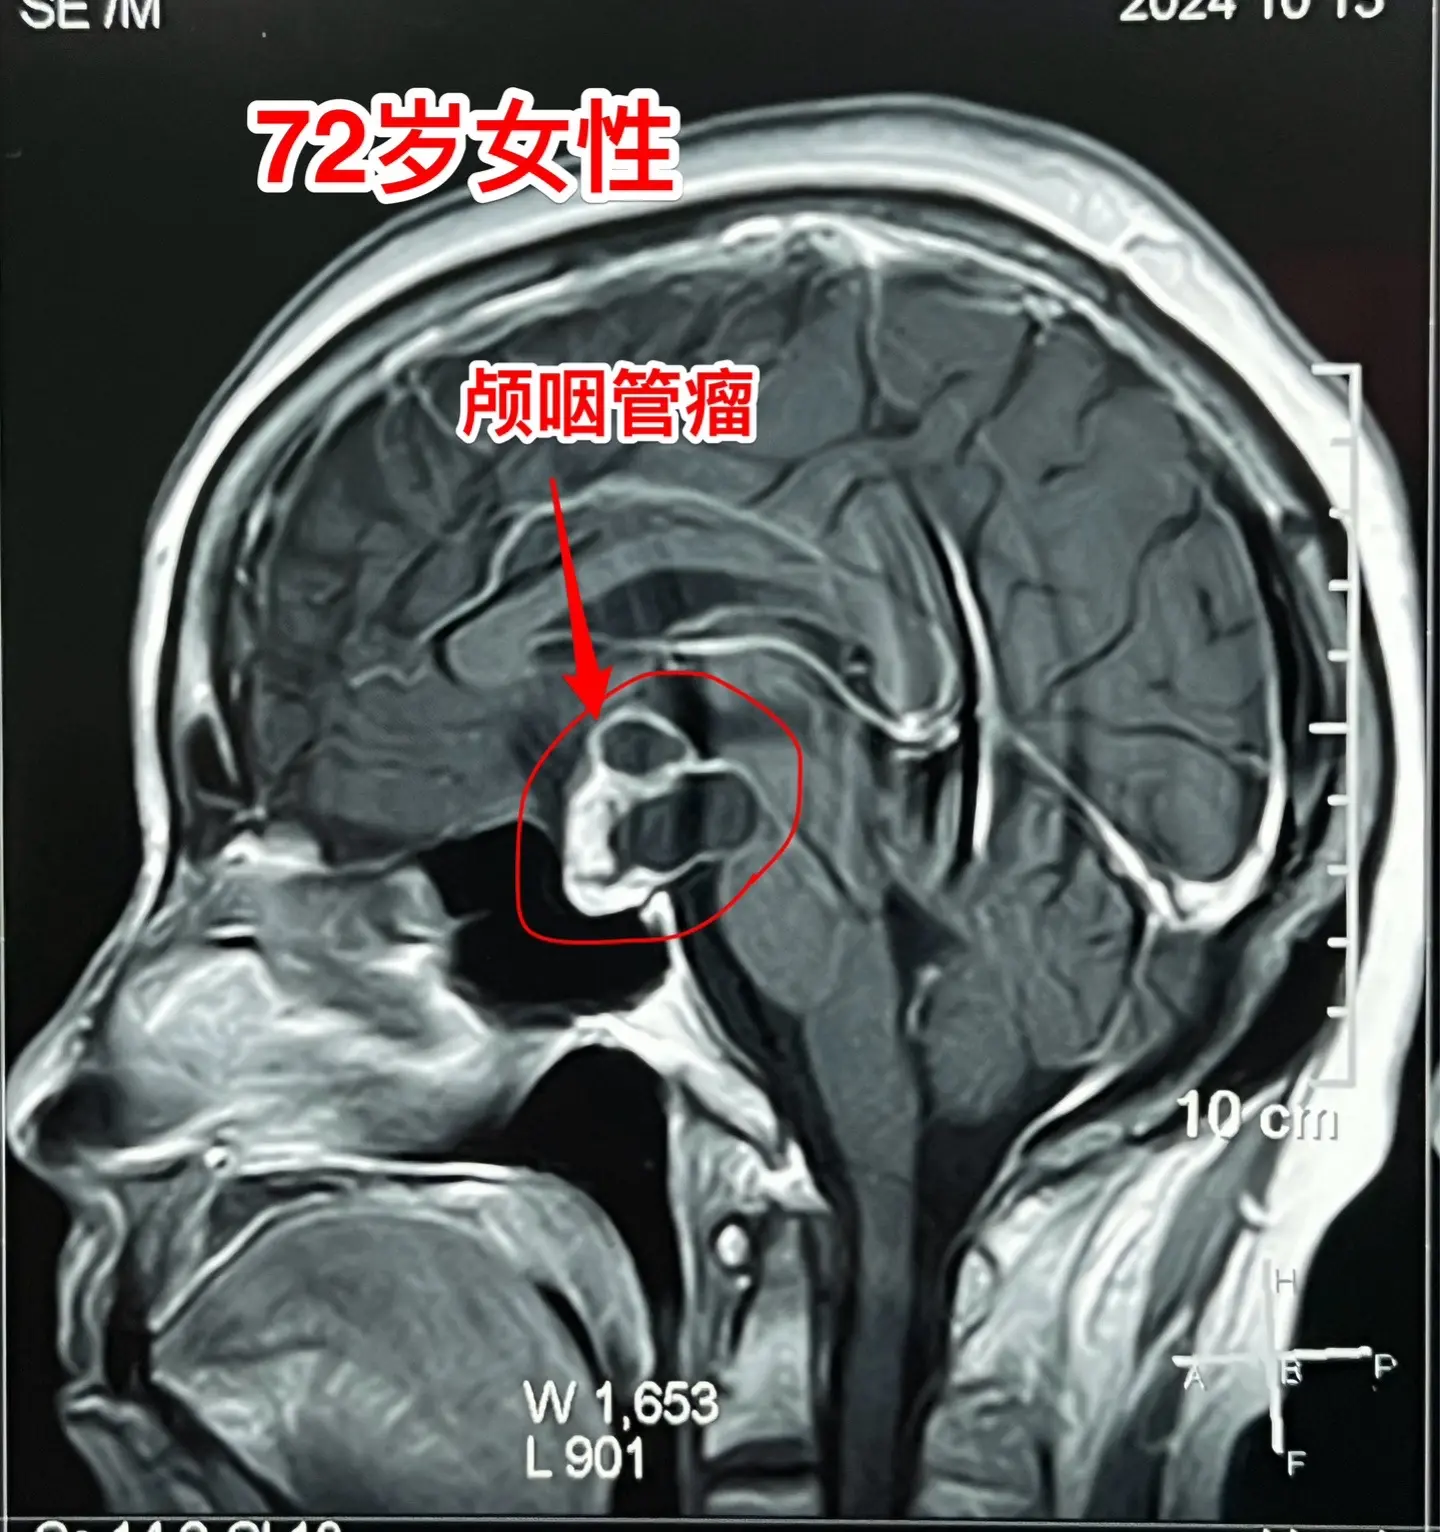

颅咽管瘤不单单是小孩子得的病!很多人认为颅咽管瘤是小孩子得的病,其实各...